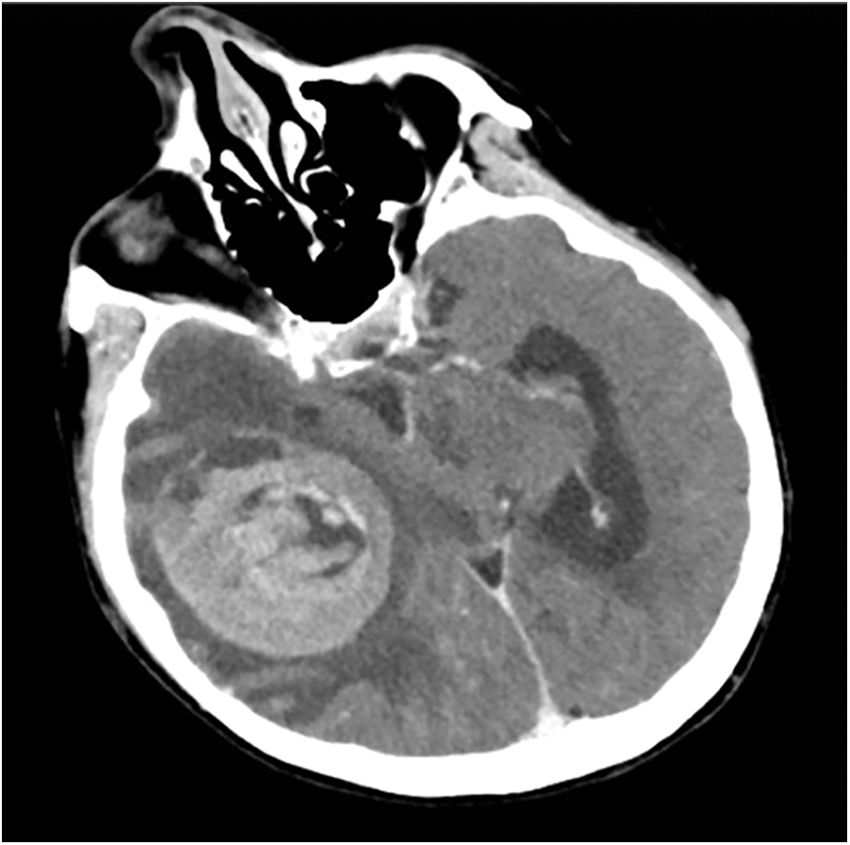

An urgent brain CT-angiography was performed, showing a well-defined right parieto-temporal intracerebral hemorrhage (6 cm × 5 cm) with intralesional calcifications, highly suggestive for a cerebral hemorrhagic cavernous malformation (Fig. 1).

Figure 1: Preoperative axial brain CT-angiogram showing a well-defined right parieto-temporal intracerebral hemorrhage (6 cm × 5 cm) with intralesional calcifications